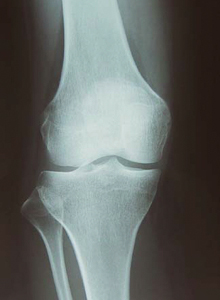

���̇B�܂��͉摜�ɂ�錟�������i�����g�Q����MRI�Ȃǁj �摜�����ł��G�ɂ̌����͂킩��܂���B

������������܂��A���E�I�ɂЂ��ɂʼn摜�����͍s���Ȃ��Ȃ��Ă��Ă��܂��B���R�͖��m�ŁA�摜�łЂ��ɂ̌����͂킩��Ȃ�����B

�ߋ����E�ό`������B�ł��ɂ݂̖����l�͎R�قǑ��݂��܂��B

�����̂��Ƃ���A�摜�ɂ��ɂ݂̌����̐����͖������܂��B

�t�Ɂu����͂Ђǂ��ό`���I����Ԃ�Ă�I�v�Ȃǂƌ����āA�s����|���ɂ��X�g���X�Œɂ݂���������P�[�X�����X����܂��B

����ȊԈ�����펯�ɘf�킳��Ȃ��ʼn������ˁB